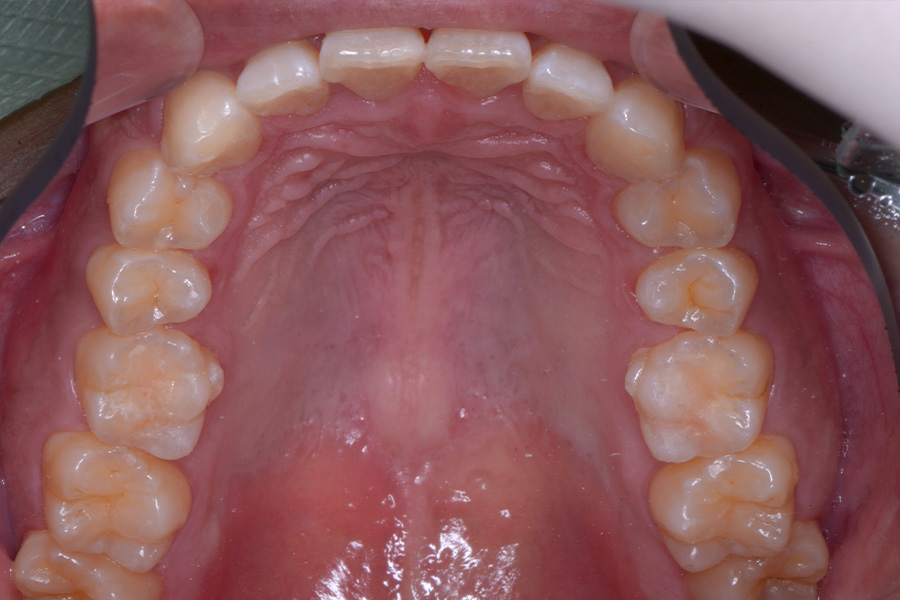

治療後

主訴 捻じれている歯を引っ込めたい

期間 8か月

費用 治療費35万円(別途調整料)

治療内容 上顎リンガル矯正(裏側矯正)